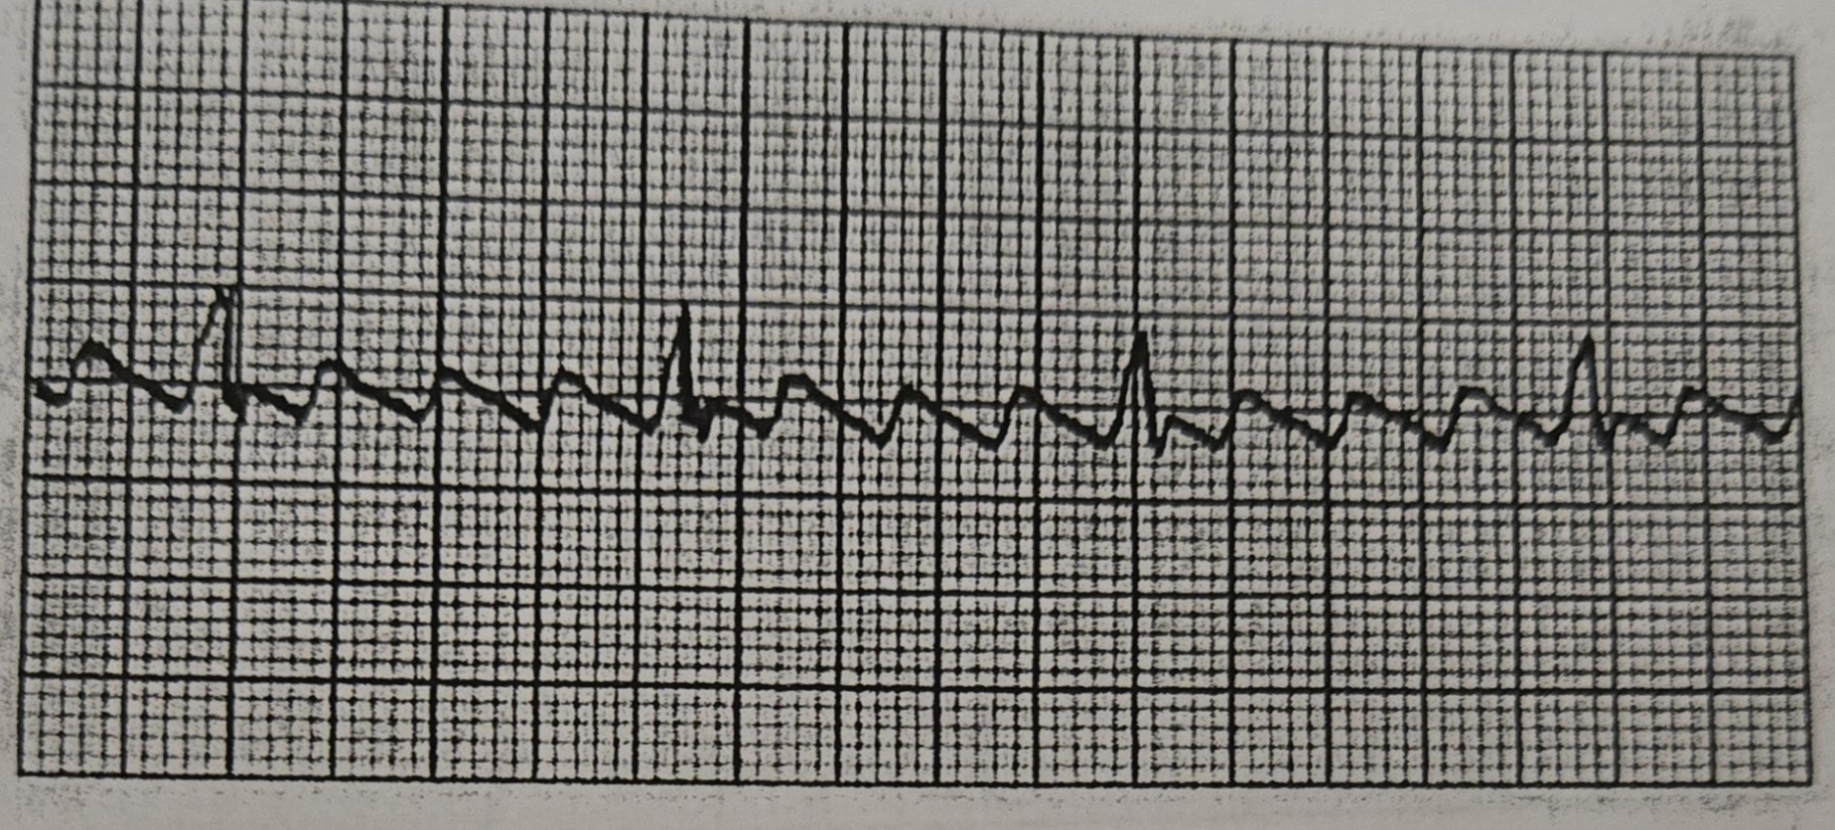

<p>What Rhythm is this?</p>

What Rhythm is this?

A-Fib